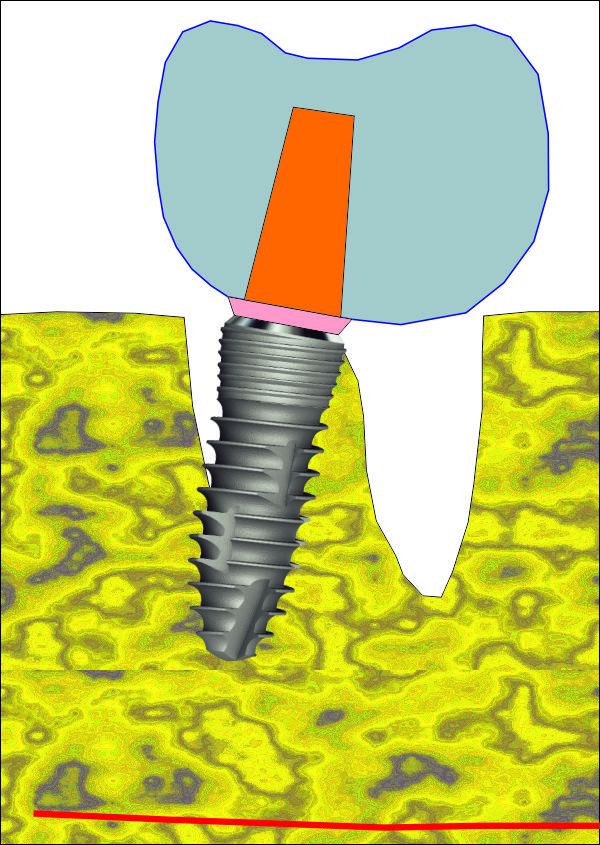

Схема на имедиатно поставен зъбен имплант от серията IS1 на производителя Neobiotech.

Вижда се как формата на импланта наподобява формата на зъбния корен - съответно

на зъбната алвеола след екстракцията на зъба при еднокоренови зъби. При

многокоренови зъби разширението на имплантатната шийка също е от полза по

отношение на имедиатното поставяне, но е необходимо да се използва доста

по-широк зъбен имплант - поне два пъти по-широк от диаметъра на корена, тъй като

долните молари са с по два корена, а при горните има също два във всяка една

равнина. Обикновено при горните молари палатиналният корен е доста по-голям

диаметър от останалите и поради това доста зъболекари препоръчват именно на

неговото място да се поставя зъбен имплант при имедиатно имплантиране. Нашият

екип не препоръчва подобен подход - в действителност диаметърът на корена е

доста голям, но при поставяне на импланта на неговото място протетичният

резултат впоследствие не е добър. Необходимо е да се изработи корона с много

голям екватор с всички негативни последици от това - трудно почистване и

опасност от постоянно разциментиране.